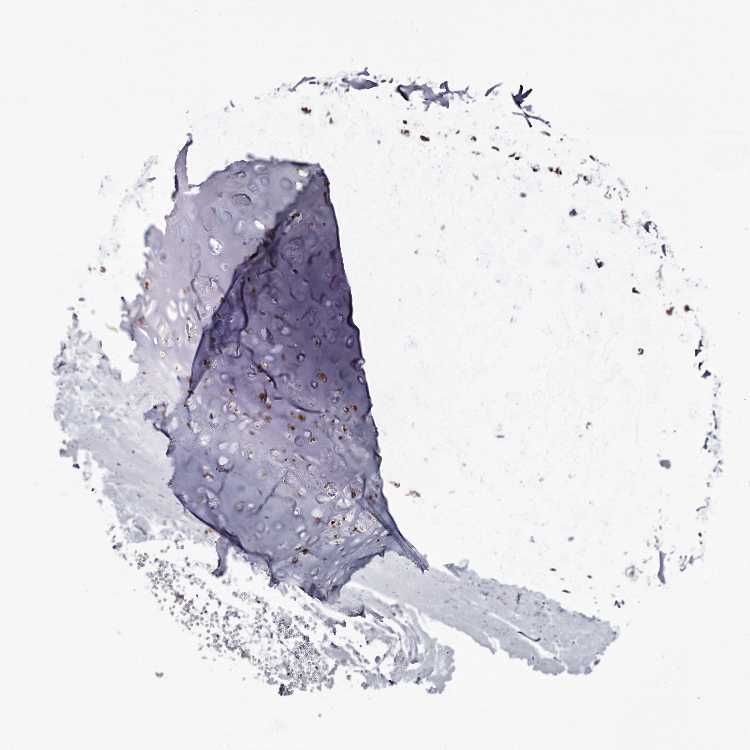

SOFT TISSUE 1 - Antibody stainingi

Antibody staining in the annotated cell types in the current human tissue is reported as not detected, low, medium, or high, based on conventional immunohistochemistry profiling in selected tissues. This score is based on the combination of the staining intensity and fraction of stained cells.

Each image is clickable and will lead to virtual microscopy that enables deeper exploration of all samples and also displays staining intensity scores, fraction scores and subcellular localization as well as patient and tissue information for each sample.

Antibody HPA037603Antibody HPA037604

Chondrocytes MediumHigh

Fibroblasts Not detected-

Peripheral nerve Not detected-